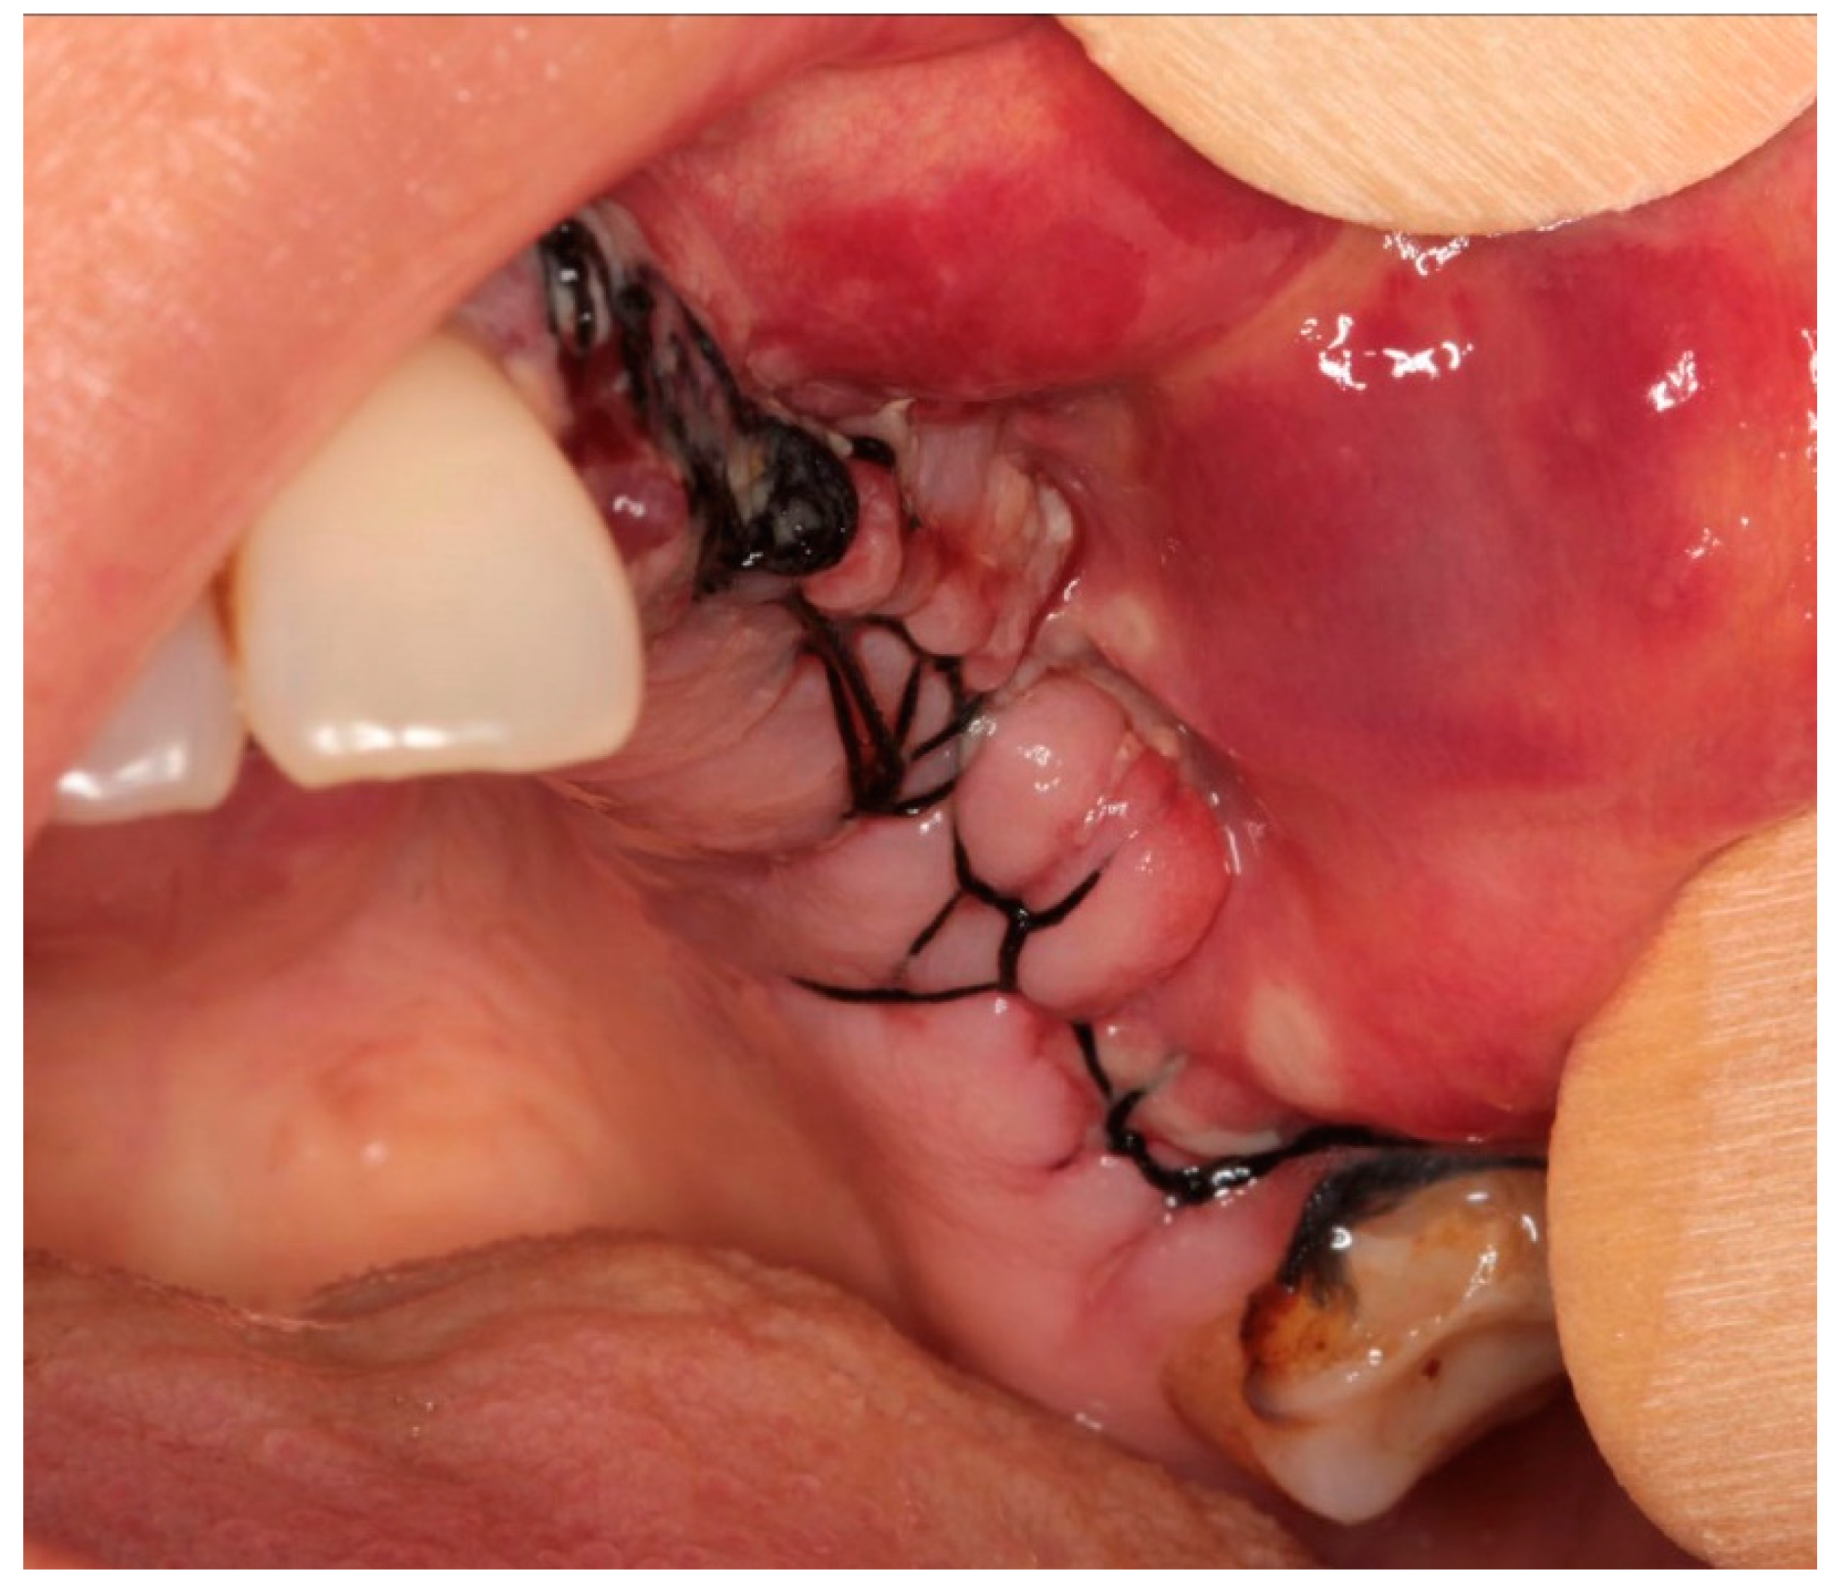

Treatment Protocol

- If complete healing is not achieved, patients are treated with surgical laser assistance.